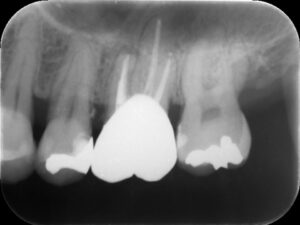

初診時レントゲン。他院にて根管治療を数か月行っているが痛みが続いていると訴えて来院。根管内には依然に詰めた薬がまだ残っているように見える。根尖部の骨破壊はほとんど認めない。

再根管治療後レントゲン。多少の違和感はあったものの、根管内部がきれいになり、排膿を認めないことから根管充填(薬を詰めること)を行った。根尖部までしっかりと薬が詰まっているのが分かる。歯根の内部がきれいな状態であれば、歯科医にはそれ以上出来ることはない。悪戯に弄り過ぎてはいけない。